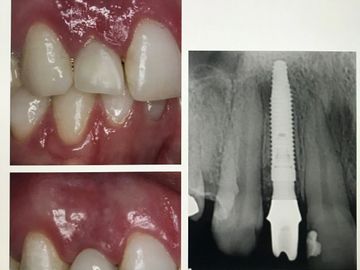

Was the implant placed Crestal or Subcrestal? The lab needs to know to create narrow emergence profile initially. Share an x-ray so lab can choose correct margin and design.

Critical that the Labs design your restoration CONCAVE at platform to emerge through bone and tissue, then change to convex shape later for tooth design and contacts.

Make sure you tell the lab the size of your healing abutment: Their final abutment will match the same emergence profile of your healing abutment. YES, your abutments will look smaller in diameter and emerge out. "Tomato on a popsicle stick"

Most important: the margin of the abutment should be 1.5mm-2.0mm above the bone AND 1-2mm below the gingival margin on buccal